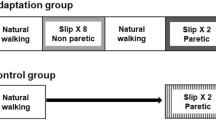

Participants were divided into two groups, a high functioning and a low functioning group, depending on their level of impairment as assessed by the Chedoke-McMaster Stroke Assessment scale (CMSA). Based on the findings from a previous study demonstrating differences in CMSA leg and foot scores between individuals with failed and successful reactive stepping response, the leg score was used to divide participants into two groups (> 4 designated as high functioning and ≤ 4 as low functioning) [33]. Participants were instructed to assume a standing position with feet shoulder width apart on the Activestep treadmill (Simbex, Lebenon, NH) which would deliver the slip-like, forward perturbation. All participants donned a safety harness suspended from the treadmill arch in order to prevent a fall where their knees would touch the treadmill belt. They were instructed to expect an unannounced slip-like perturbation at any instance. Participants were asked to perform their natural response to recover from the perturbation and prevent themselves from falling. After familiarization trials, participants were subjected to a pre-training trial at the highest intensity (level III), followed by five perturbation trials given at one lower intensity (level II). During these trials, if participants experienced more than three falls, they were assigned to be trained at a lower perturbation intensity (level I), whereas the rest of the participants continued to receive the remaining training at level II to complete the protocol consisting of a total of 11 slip trials. Thus, those participants who did not tolerate the higher intensity were exposed to 11 more slips at a lower intensity (S1’-S8’; S9’-11′) whereas, for the participants who tolerated the high intensity, these 5 trials were considered a part of the high intensity training arm and they received 6 (S6-S8; S9-S11) additional trials at this intensity (Fig. 1a).

a Shows the research design and experimental protocol along with the intensities of perturbation for pre-training, training, post-training, and retest trials. The mark ‘indicating perturbation trials at lower intensity. b Shows the trajectory of belt displacement and the velocity profiles for the different perturbation intensities (level I, II and III) used for assessment and training

Following the initial eight slip trials, all the participants were made to walk at their self-selected natural speed for two trials which served as wash-out trials in order to reduce anticipation of the upcoming perturbation. After training, both groups were subjected to a post-training trial at the pre-training intensity (level III for high intensity training arm and level II for low intensity training arm) to examine scaling of the recovery response. Three weeks after training, participants from both groups were re-tested in order to assess the training retention. At this re-test, each participant received a single slip perturbation at the pre-training perturbation intensity (Fig. 1a). During the training and testing sessions, participants were intermittently asked if they experienced any pain, discomfort, fatigue or fear and would like to discontinue. All the participants consented to complete the protocol.